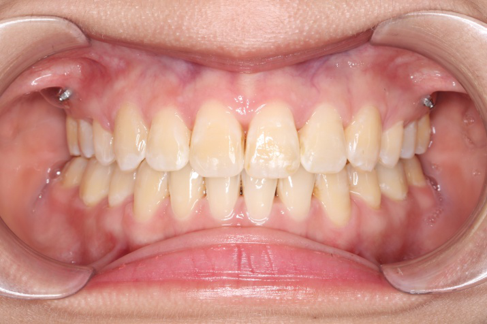

2018.11.14  术后侧面改善明显,露龈笑改善明显,笑弧笑线协调,颏部肌肉紧张度明显改善

2018.11.14  术后磨牙尖牙I类关系,中线齐,覆合,覆盖正常

宏观评价:面部对称,面下三分一比例协调,上下唇凸度正常,上颌牙列内收转矩控制良好,下颌后缩改善,颏唇沟变得更加柔和,术后达到基本直面型。

迷你观评价:上下牙齿中线与面中线对齐,笑弧协调,微笑时牙龈暴露量正常,微笑时横向正常,左右唇基本对称。

微观评价:牙齿整齐,咬合关系良好,上下前牙转矩及突度控制良好,磨牙关系I类,尖窝咬合关系良好,OB,OJ正常。